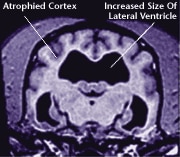

Older Brain with Damage

MRI scans show loss of brain tissue in affected dogs.

Note: MRI scans are not harmful to dogs.